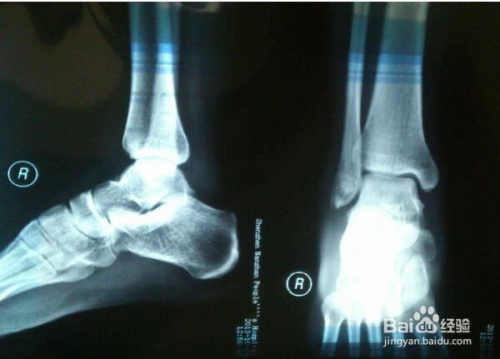

脚受伤后,我第一时间去医院寻求了专业医生的帮助,医生对我的伤势进行了详细的检查,并给予了我专业的治疗建议,在治疗过程中,我深刻体会到了科学治疗的重要性,小伙伴们如果遇到类似情况,一定要及时就医,听从医生的建议,进行科学治疗。